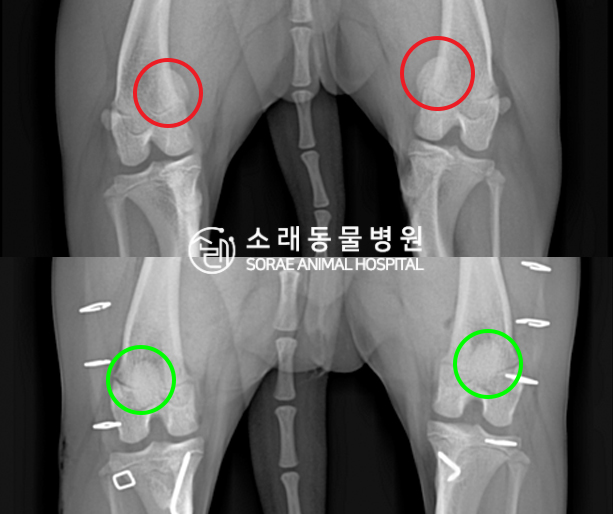

수술전과 수술후에 촬영한 콩이의 슬개골

방사선 사진입니다. 나란히 놓고 비교해보니

슬개골의 위치에 확연한 차이가 있는 것을

확인해 볼 수 있는데요. 내측으로 탈구되어 있던

슬개골이 원래 제자리인 활차구에 예쁘게

자리 잡고 있는 모습을 확인할 수 있었습니다.